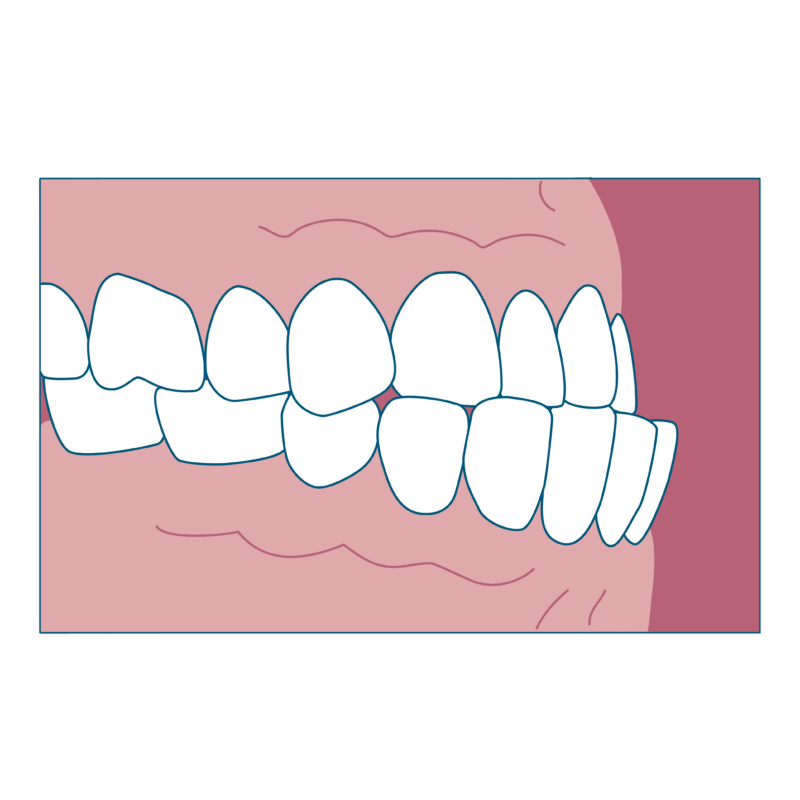

受け口とは、下の前歯が上の前歯より前に出ている状態のことを指します。専門用語では反対咬合(はんたいこうごう)と呼びます。また、歯だけでなく下あごが上あごより前に出ている状態を下顎前突(かがくぜんとつ)と呼びます。

- 真横から見たときに下あごが前に出ているように見える

- 食べ物を前歯でかみ切りにくい